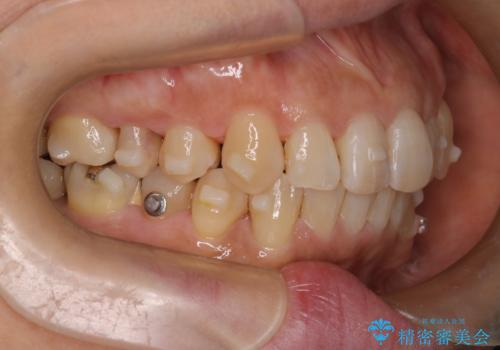

インビザラインで非抜歯矯正|ゴムかけで下顎犬歯の低位を改善し、噛み合わせも最適化

- 患者様は、下顎の犬歯が通常より低い位置にあり、噛み合わせのバランスが崩れていることを気にされて来院されました。診査の結果、抜歯せずに歯をきれいに並べるスペースを確保しながら、**ゴムかけ(顎間ゴム)**を使用して下顎犬歯の高さを適正に調整する方針を立てました。併せて、奥歯の噛み合わせも改善し、全体のバランスを整えることを目標としました。

治療はインビザライン(マウスピース矯正)を使用し、歯列全体を計画的に移動させながら、下顎犬歯の低位をゴムかけによって徐々に引き上げました。患者様にはゴムの装着をしっかり継続していただき、順調に改善が進行。最終的に奥歯の噛み合わせも安定し、全体の咬合バランスが整いました。治療後は「自然な噛み心地になり、見た目も満足」と患者様にも喜んでいただきました。